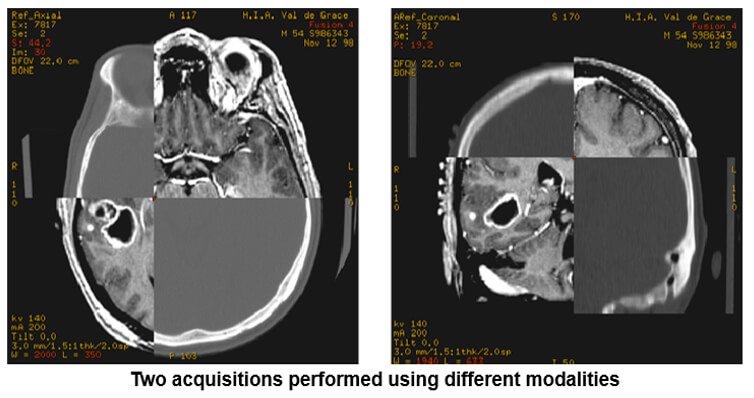

Image Fusion

After fixing three landmarks (or points) in the anatomy, the system readjusts the plans with a maximum tolerance of 20*.